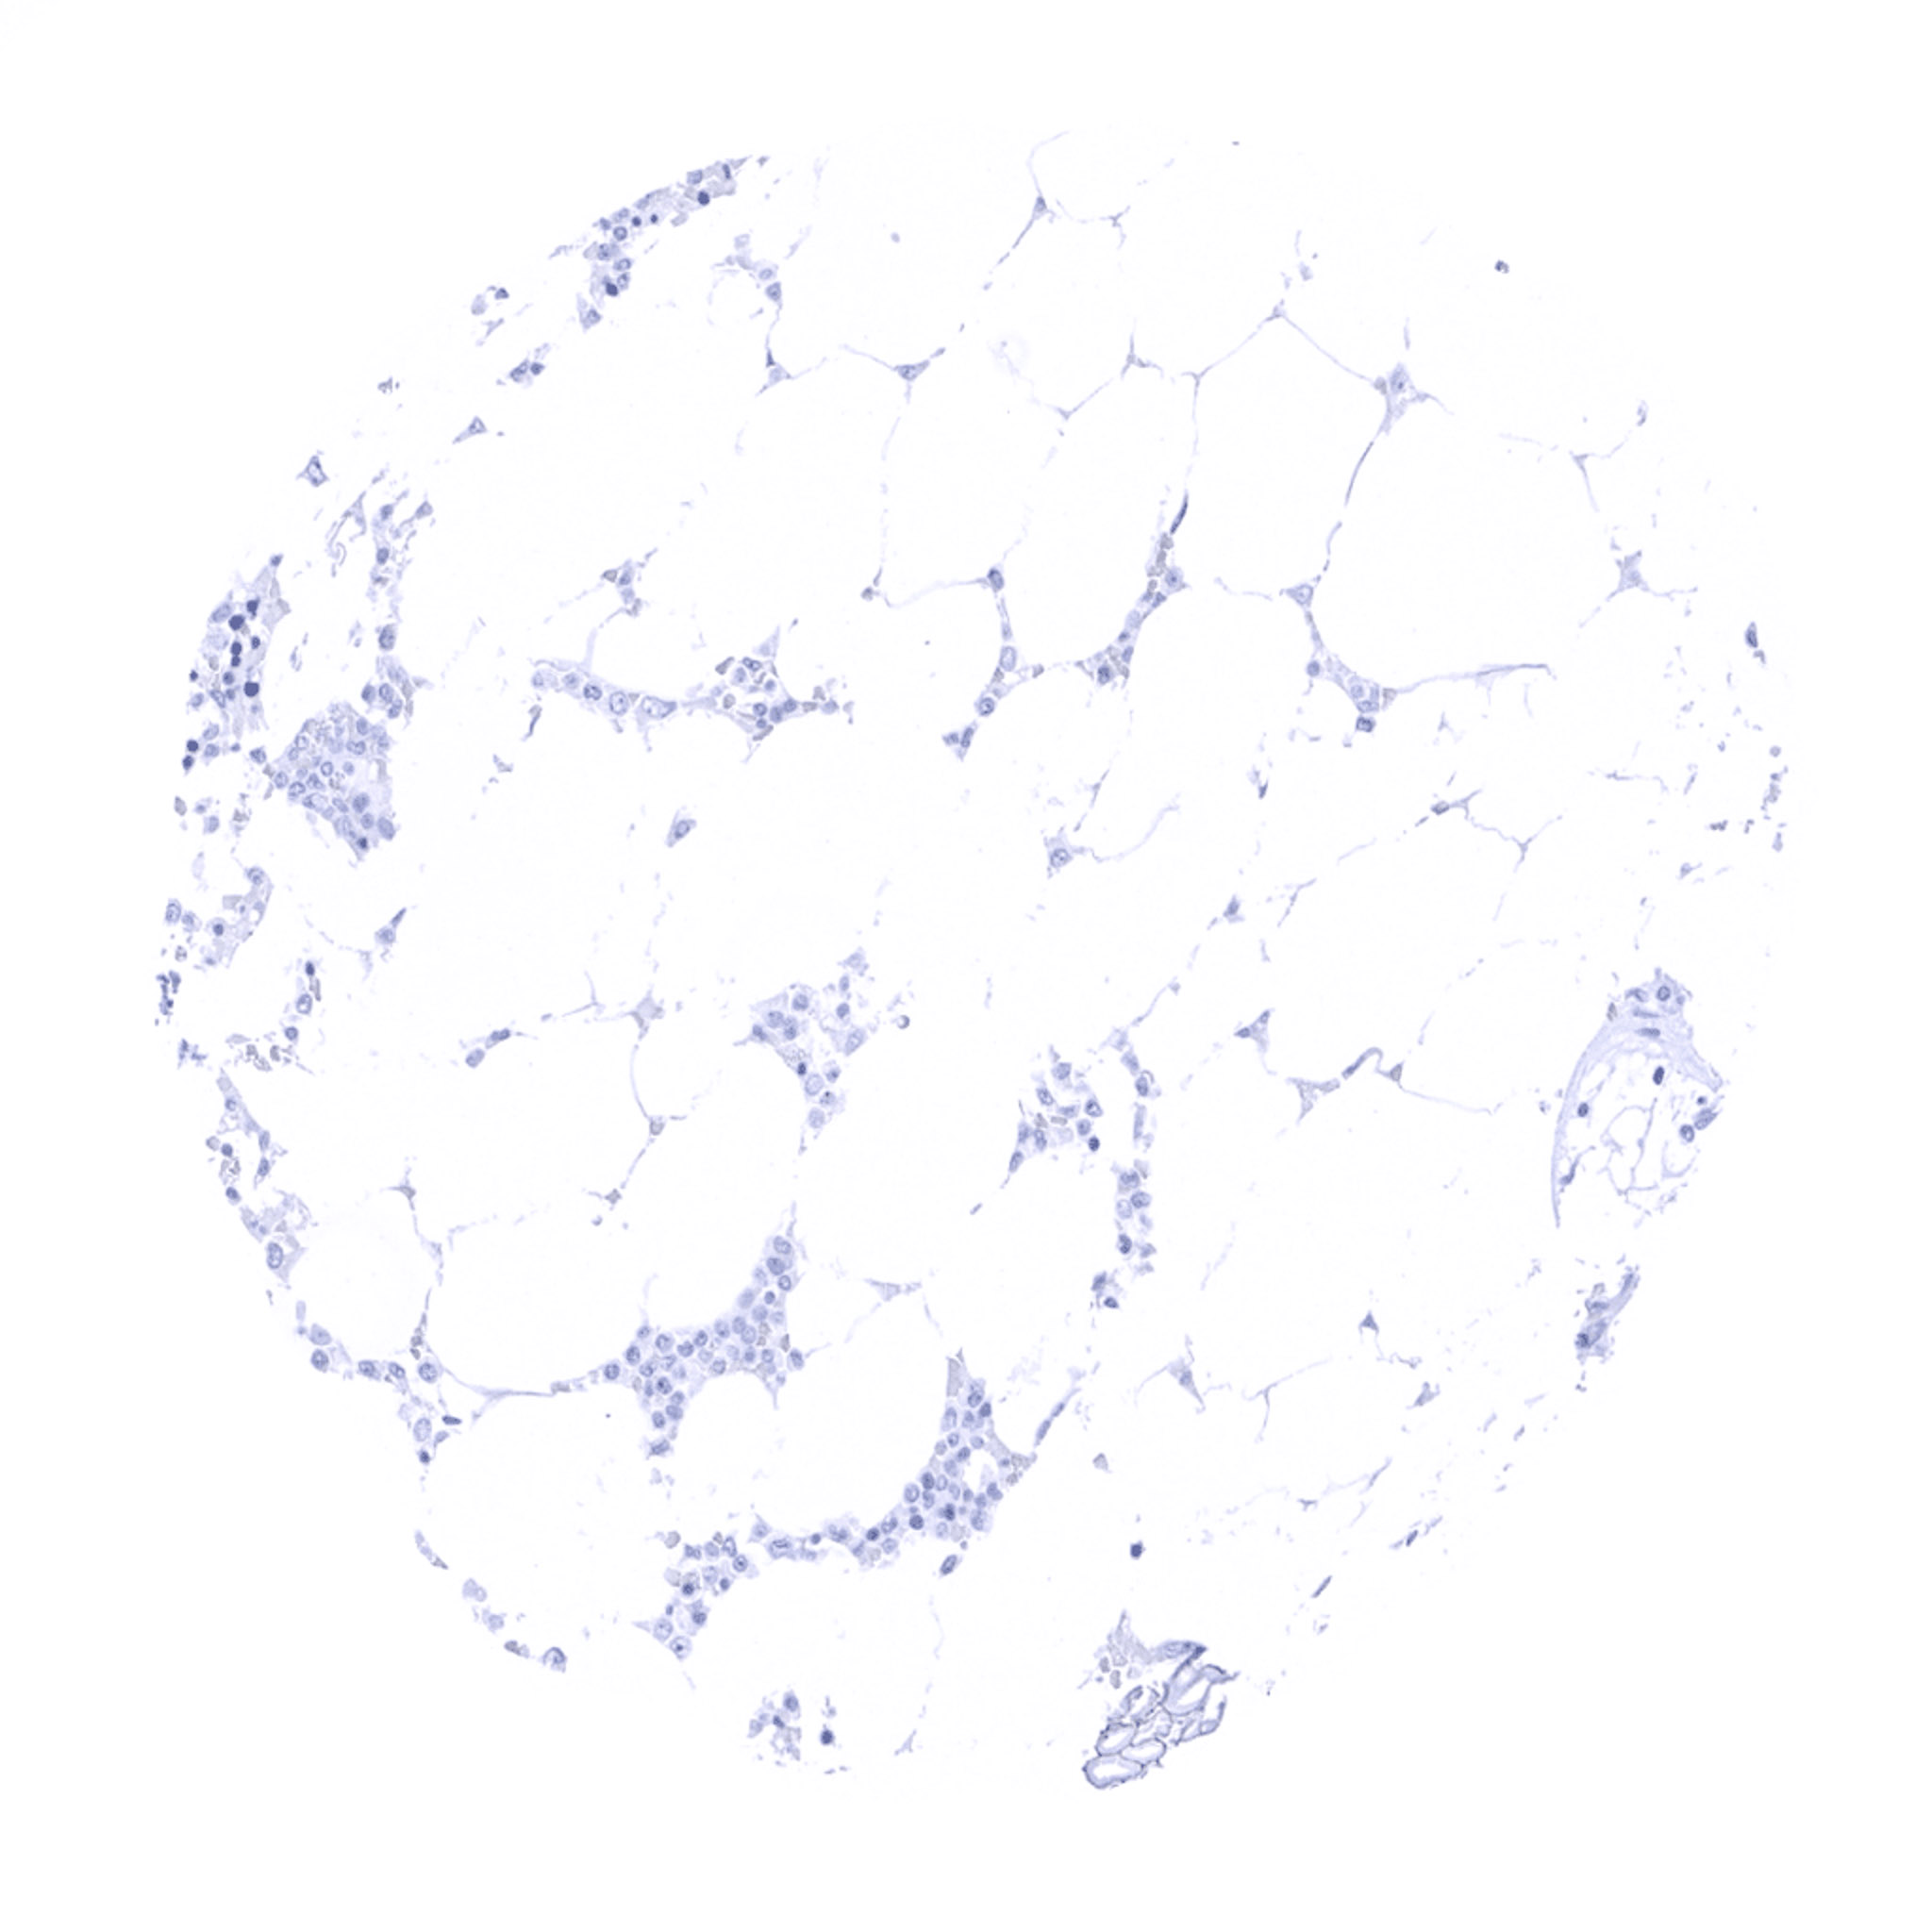

Fat